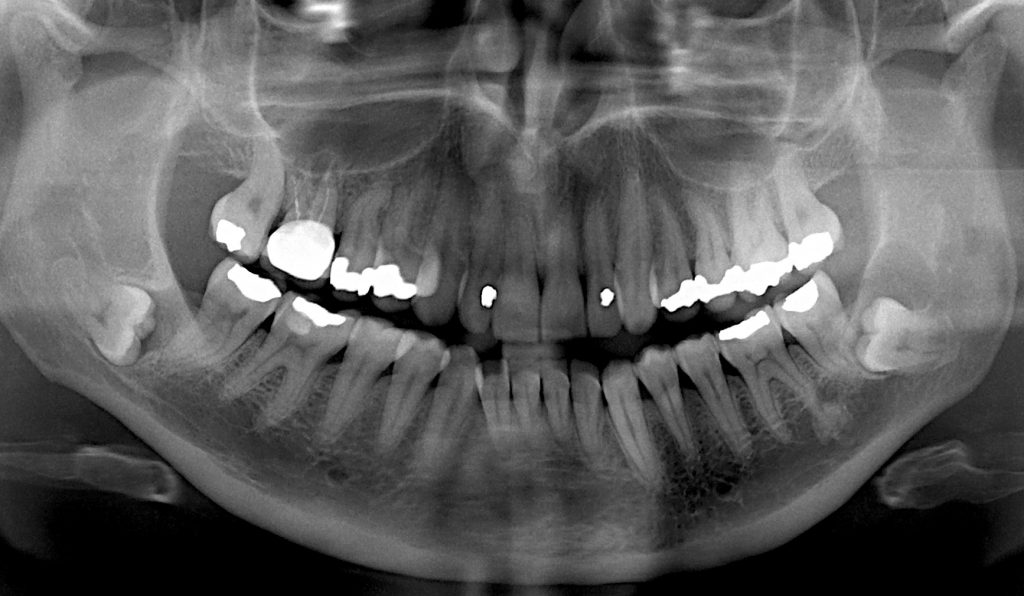

Corso base di Endodonzia

PRATICA: pratica su denti estratti DIDATTICA: teoria, video e interventi in diretta TUTORAGGIO: discussione dei casi e study club Programma 1° INCONTRO […]